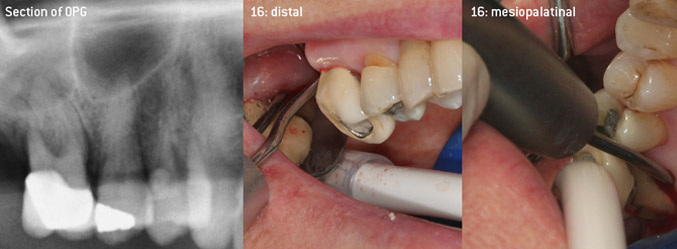

Come pionieri dello sviluppo della nuova punta per ablatori 3AP diamantata, i due dentisti hanno riconosciuto la necessità di migliorare le restrizioni di manipolazione delle punte diamantate disponibili in commercio, specialmente durante il trattamento della forcazione e lavorando su tasche intraossee strette. Tutto ciò deve essere fattibile sia per procedure non chirurgiche (figura 2) sia per procedure chirurgiche (figura 3).

debridement aperto delle forcazioni sui denti 16 e 17

Fig. 3: debridement aperto delle forcazioni sui denti 16 e 17 in caso di una perdita avanzata di attacchi

(Foto (figure 2-4): © Dott. Christian Graetz)